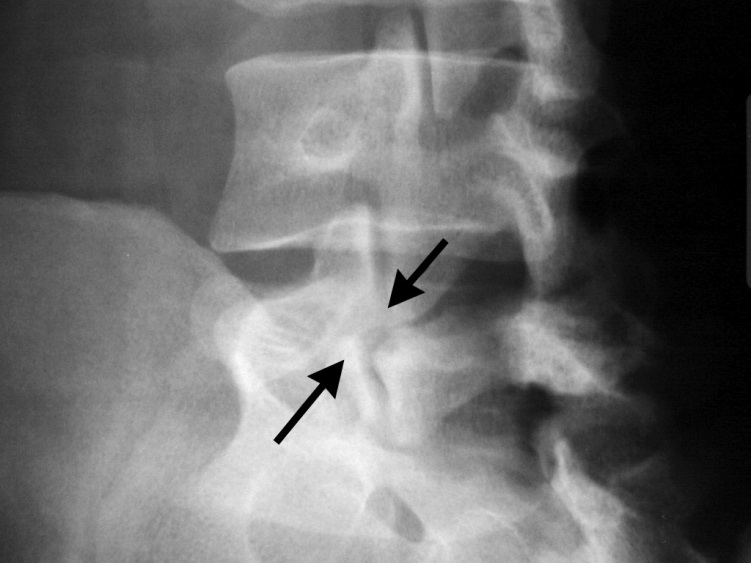

- RTG skośne celowane na cieśń łuku przy podejrzeniu kręgoszczeliny, terier sign : objaw „szkockiego teriera” – kręgoszczelina widoczna jest jako przerwanie szyi w figurze teriera